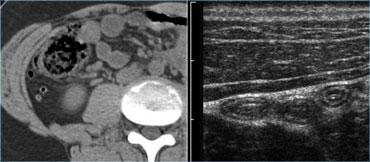

Bên trái là hình ảnh bệnh nhân với tiền sử đau hố chậu phải 4 ngày.

Khám lâm sàng phát hiện viêm phúc mạc.

Tốc độ máu lắng là 48mm/giờ. Khám bụng không đáng tin cậy.

Phẫu thuật cắt ruột thừa kết hợp dẫn lưu áp xe sau đó được thực hiện mà không gặp khó khăn kỹ thuật.

Trước khi dẫn lưu qua da, cần chụp CT để xác định phạm vi của áp xe và xác định đường tiếp cận an toàn nhất.